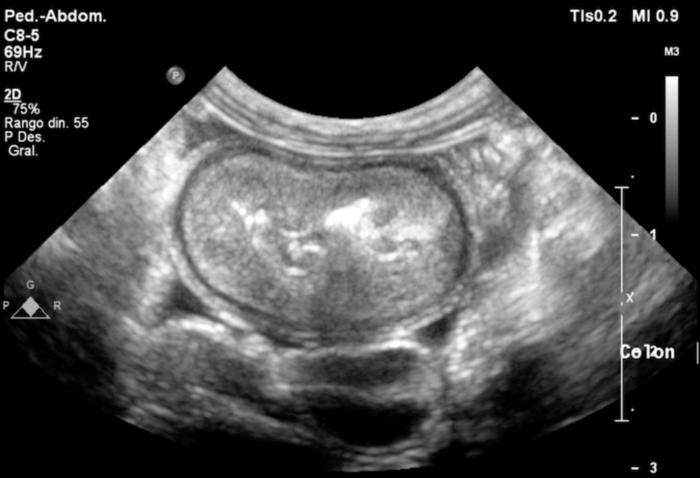

La ecografía abdominal mostró un engrosamiento marcado de la pared del colon, especialmente en el ciego y el colon descendente, con pérdida de la diferenciación normal de capas (Figura 2-3). También se observó linfadenomegalia mesentérica y una pequeña cantidad de líquido libre abdominal (no muestreable). Estos hallazgos reforzaron la sospecha de enfermedad inflamatoria intestinal, principalmente afectando al intestino grueso.